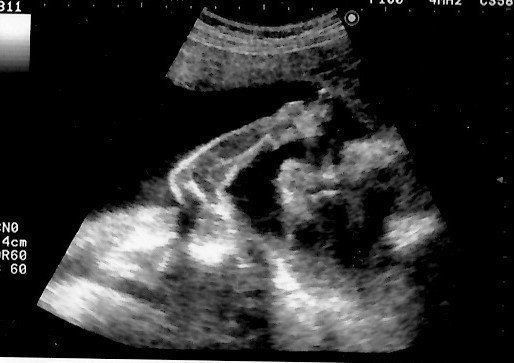

妊娠9週目のエコー写真 胎児の姿が見えてきた!

エコー画像で頭と胴体が分かれた人間らしい姿を見て、いよいよ妊娠したという実感がわいてきました。それと同時に、このまま無事に育ってくれるのだろうかという不安で毎日祈るような気持ちでいました。いまだにこの画像を見るたびに、この時の不安でたまらなかった自分の気持ち、そして生命の神秘を目の当たりにしたときの厳粛な気持ちを思い出し、胸がいっぱいになります。